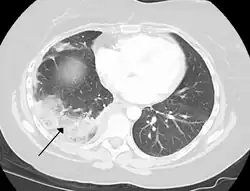

Chest CT (axial lung window) -

Chest CT (axial lung window)